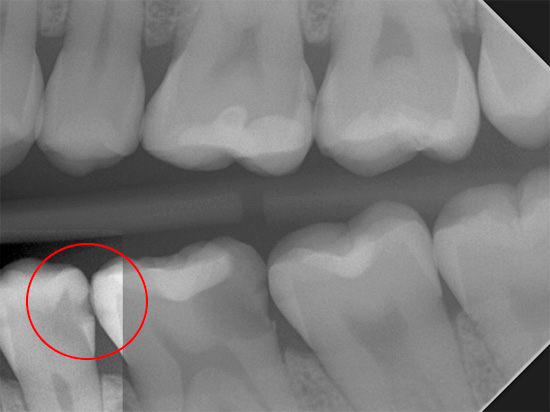

Ad esempio, la foto sotto mostra una radiografia di un dente con una cavità cariata nascosta:

Se si verificano danni allo smalto sulla superficie approssimativa del dente, può essere estremamente difficile discernere tali carie anche con uno specchio dentale.

Ad esempio, nella radiografia in basso, una cavità cariata nel dente è chiaramente visibile, che non è stata rilevata con un semplice esame visivo:

Una radiografia è particolarmente utile per rilevare la ricorrenza della carie, nonché la carie radicolare e la carie prossimale. Ad esempio, ecco una foto in cui puoi vedere come appare la carie approssimativa nell'immagine: